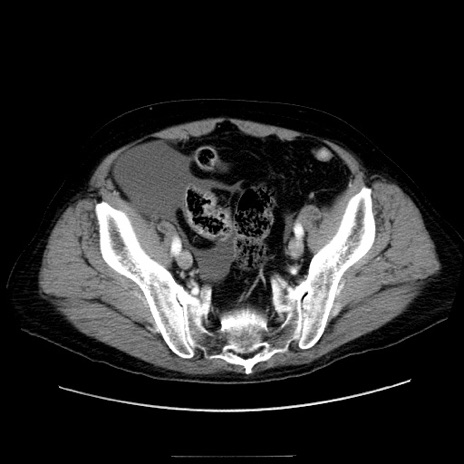

症例30(横断像)

【症例】80歳代男性

【主訴】臍周囲痛

【現病歴】約6時間前から臍下部痛が出現。次第に腹部膨隆・背部痛も生じてきたため来院。背部痛の場所は変化しない。

【身体所見】意識清明、BT 36.3℃、BP  131/87mmHg、P 87bpm、SpO2 100%(RA)、臍周囲自発痛・圧痛あり、反跳痛なし、自発痛部位に一致して板状硬あり、腹部膨隆、腸雑音減弱、CVA tenderness両側陰性。